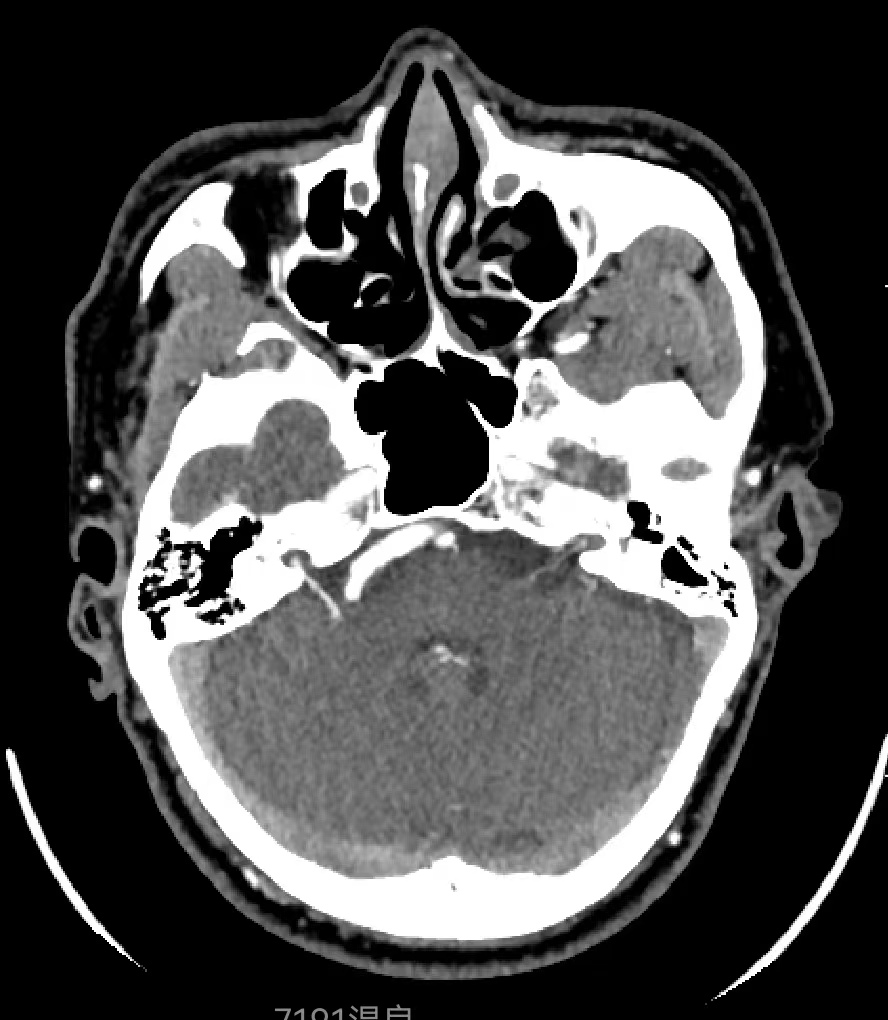

患者,男性,46岁,因“右侧面肌痉挛5年”就诊。查体右侧可见典型的面肌痉挛表现。当地医院MRI可见右侧椎动脉与面神经关系密切,我院行CTA检查可见内听道附近椎动脉扩张、迂曲,与面神经关系密切,与当地医院MRI相符。